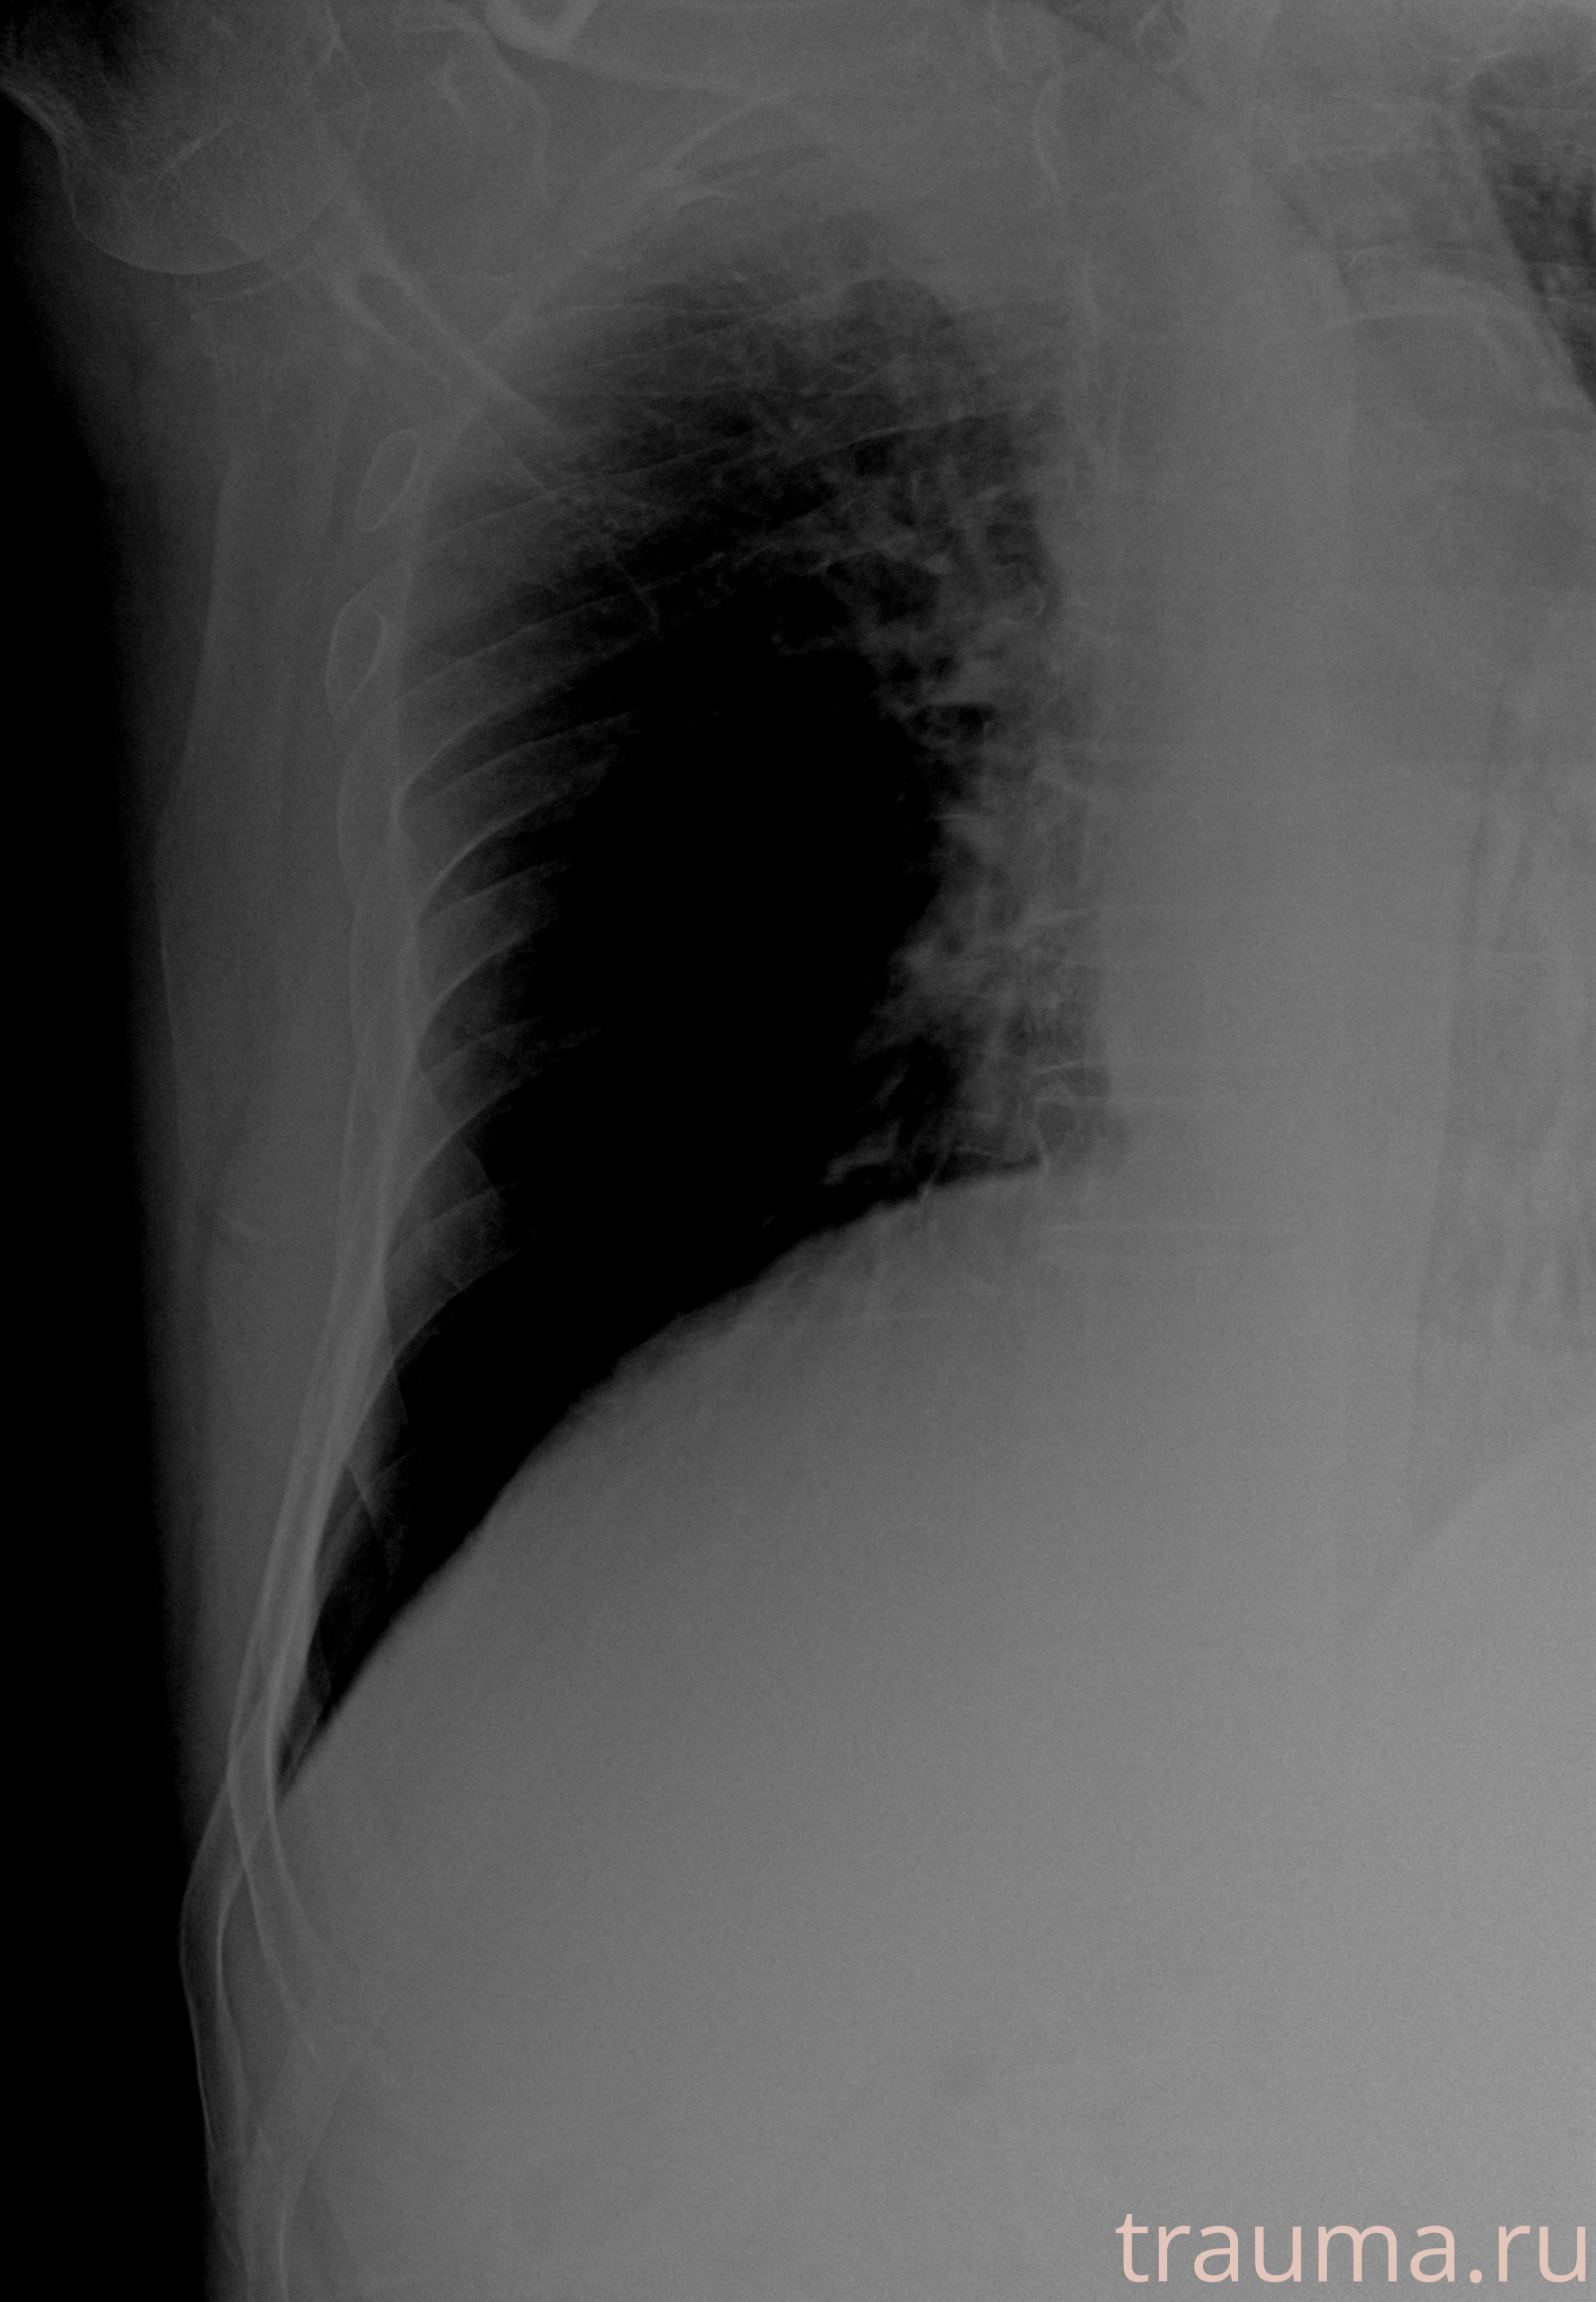

Рентгенограммы

Рентген на дому: по вашему адресу приезжает врач-рентгенолог, травматолог-ортопед с мобильным рентгеновским аппаратом, проводит диагностику травмы или заболевания, делает необходимые рентгенограммы, дает рекомендации по дальнейшему лечению. Получить качественные снимки в домашних условиях возможно благодаря уникальной методике, разработанной МосРентген Центром для института  Склифосовского

при переломе шейки бедра и пневмонии от компании МосРентген Центр - партнера Института имени Склифосовского